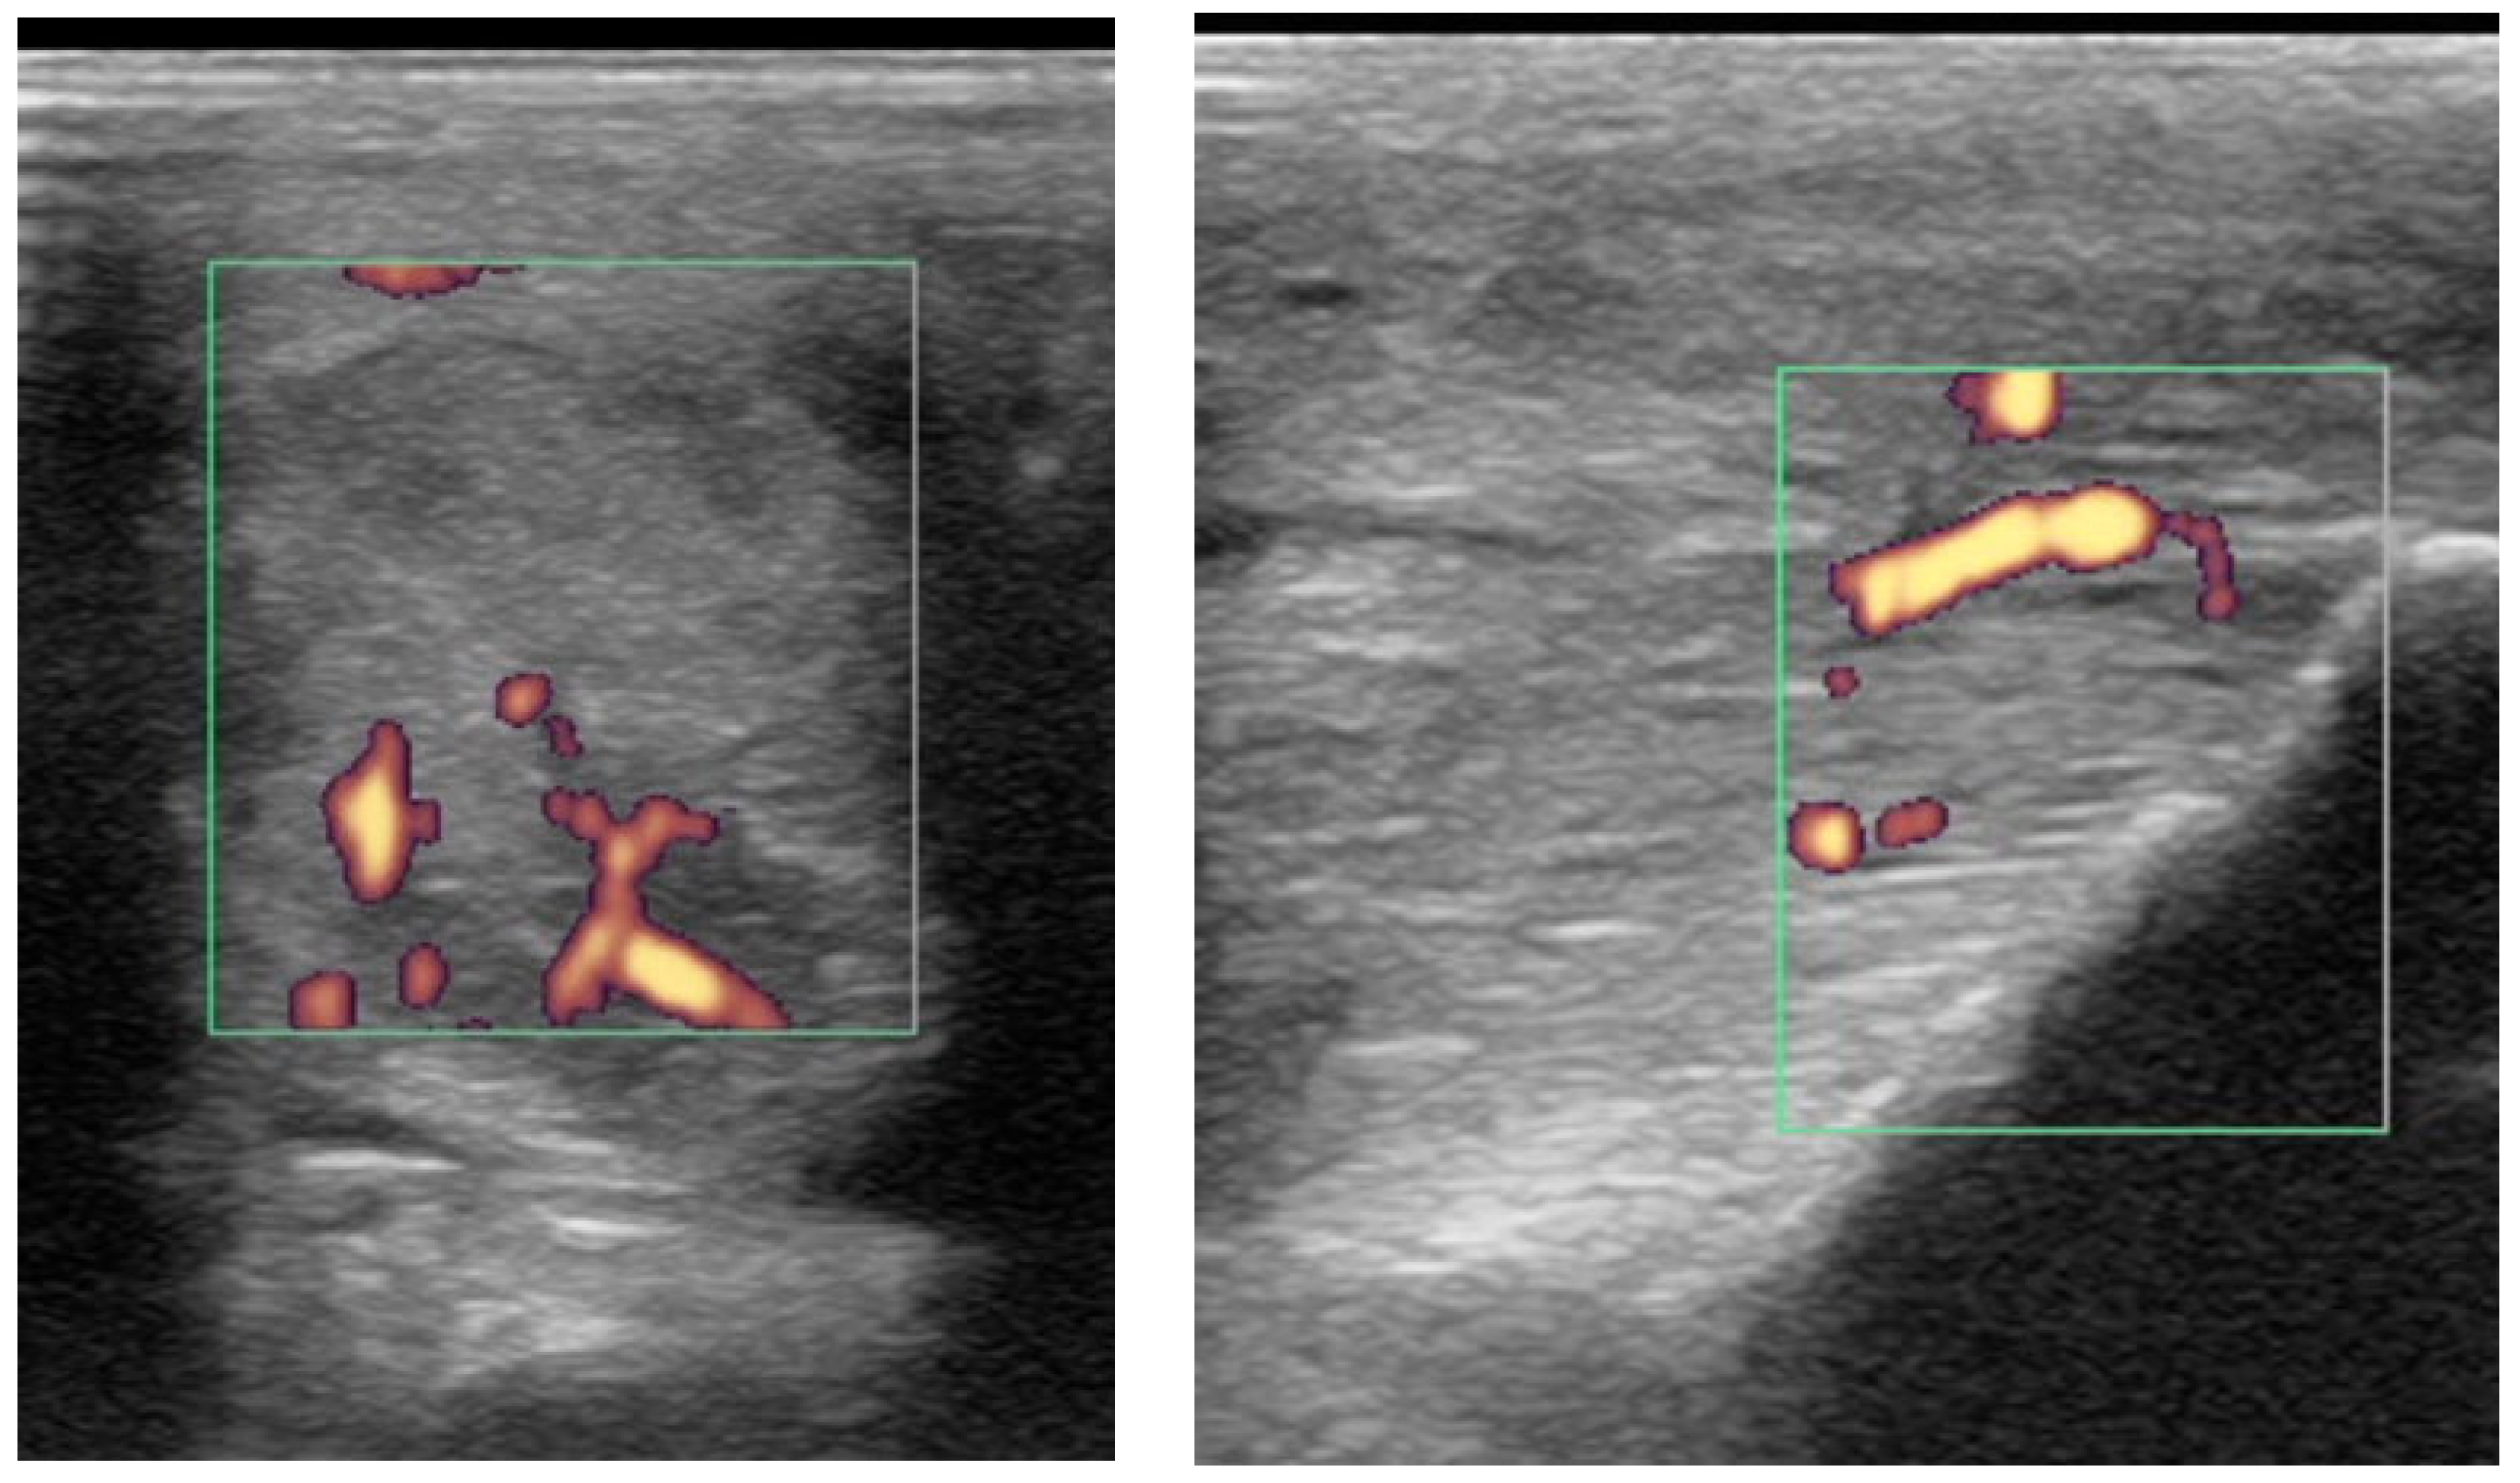

Power Doppler examination was performed in 62/89 branches (67.4%). Doppler signal was present in 59/62 (95.2%) branches (Figure 5, Figure 6, Figure 7 and Figure 8) and absent in three branches. At the initial examination, Doppler signal was classified as mild in 22/62 branches (35.5%), moderate in 25/62 (40.3%) and severe in 12/62 (19.4%) branches. Doppler signals persisted in follow-up examinations, despite treatment, in 17/62 branches (27.4%) (Figure 7).

Figure 7. Transverse (left) and longitudinal (right) ultrasonographic images of the lateral branch of the suspensory ligament (SL) of a hindlimb of a 15-year-old purebred Spanish horse (PRE), acquired 2 weeks after injury, with a non-healing suspensory branch desmitis. The SL branch is enlarged with large hypoechoic regions and loss of long linear parallel echoes in the longitudinal image. There is also substantial subcutaneous echogenic tissue consistent with periligamentous fibrosis. Power Doppler signal was graded severe and persisted despite treatment. The horse was retired.

The severity of power Doppler signal was not associated with outcome (p = 0.20); however, 56% of horses with severe power Doppler signal were retired compared with 22% with moderate signal and 12% with mild signal. Persistent Doppler signal over time was associated with follow-up outcome (p < 0.001) (Figure 10). In particular, post hoc testing showed that significant differences were present for associations between the good (p = 0.001) and retired (p = 0.04) outcome categories and Doppler signal persistency, but not the poor (p = 0.25) outcome category. Only 6/17 (35.2%) of horses with persistent Doppler signal (Figure 7) had a good outcome, whereas 11/17 (64.7%) had a poor outcome or were retired.

4.3. Monitoring: The Use of Power Doppler in Non-Healed Cases; Uncontrolled Inflammatory Response

In the current study, most SL branches with persistent hypoechoic lesions over time, which suggested an absence of healing, also maintained severe Doppler signal affecting a large part of the ligament. No decrease in signal intensity and area affected was observed during serial examinations. In human medicine, prolonged vascularity is common in persistent inflammatory enthesitis, such as in rheumatoid patients [39]. It is thought that this reflects a dysregulation between inflammatory mediators and inhibitors, instead of a normal process of repair and remodelling after injury. The tendon or ligament remains in a persistent inflammatory status with pain on palpation [3].

In the current study, the non-healed SL branches occurred more commonly in hindlimbs than in forelimbs (n = 4 and n = 2, respectively). In the hindlimbs, all non-healed SL branches had an increased size, periligamentous fibrosis, severe heterogenicity and persistent severe power Doppler signal despite treatment. Periligamentous fibrosis increased over time, probably in an attempt to limit fetlock hyperextension. The non-healing forelimb SL branches remained enlarged with heterogenous echogenicity and persistent power Doppler signal, as reported in human in degenerative lesions [35].